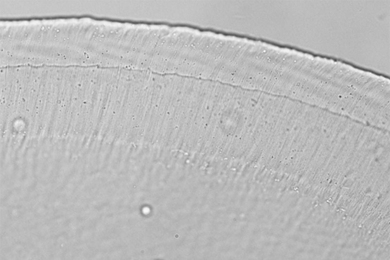

MIT researchers have found that a small gelatinous structure, called the tectorial membrane, gives the human ear its extraordinary ability to detect faint sounds, reports the Xinhua news agency. The findings “could help devise ways to treat hearing impairment via medical interventions that alter the pores or the properties of the fluid in the membrane.”